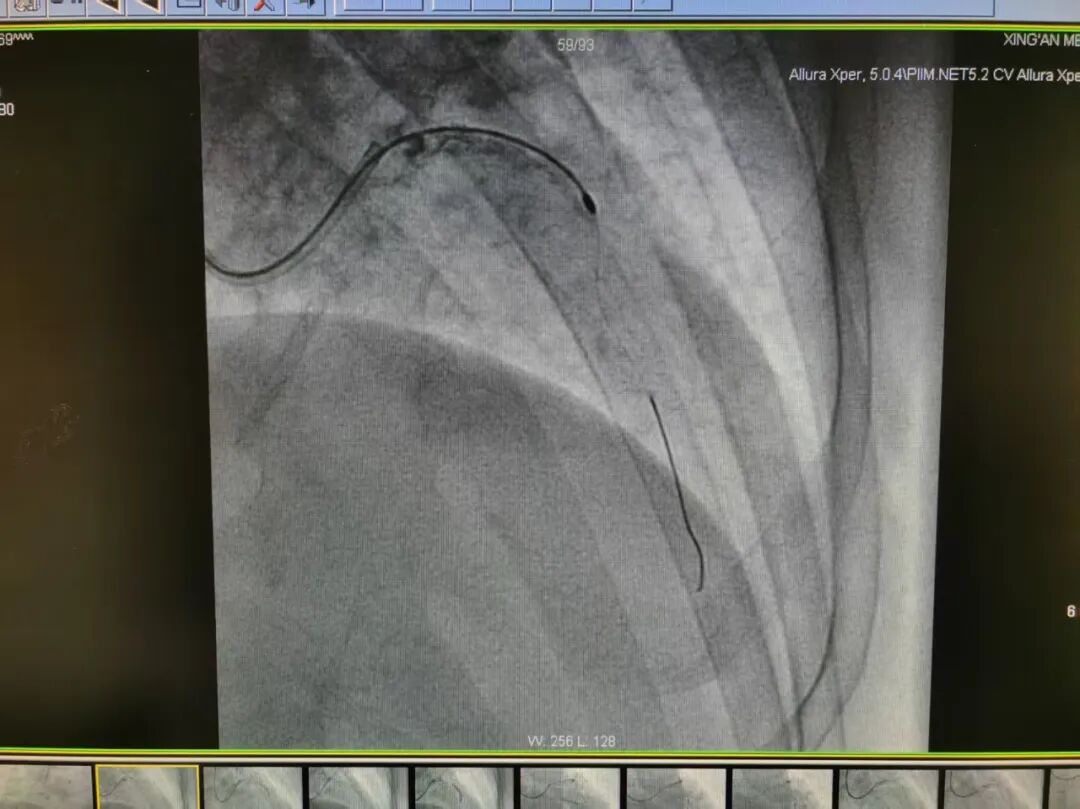

在介入治疗过程中,团队遇到了棘手难题:由于前降支钙化严重、血管管腔极度狭窄,最小型号的扩张球囊也无法顺利通过病变部位,常规支架植入手术难以实施。面对这一困境,冯源海主任团队与葛海龙教授紧急讨论,结合患者病情特点,最终确定采用冠脉旋磨术这一先进技术方案。

手术中,葛海龙教授全程指导,冯源海主任团队精准操作,经过精准旋磨后,前降支管腔狭窄程度得到显著改善,血流通畅性恢复,随后团队顺利完成球囊扩张及支架植入术。整个手术过程顺利,患者生命体征平稳,术后恢复良好,胸痛症状已明显缓解。